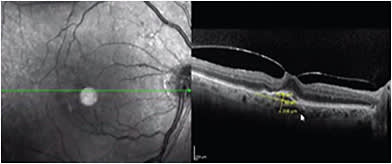

DME AND WET AMD

Although it is uncommon in clinical practice, double pathology can exist, and a patient who has been treated for DME can live long enough to develop CNV due to wet AMD or other neovasculopathies (Figure 5). Although it has been reported that diabetic retinopathy can be a protective factor against the development of AMD, there has been much debate on this issue. Management is likely to stay the same (injections), but you must discuss the prognosis with your patient.